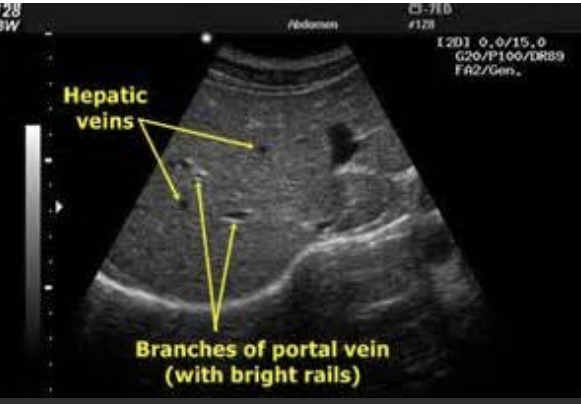

Liver

coarsely grained

large vessels, gallbladder is visible

diaphragm lies beneath the liver

portal veins have clearly defined, bright, hyperechoic walls

hepatic veins have poorly defined walls